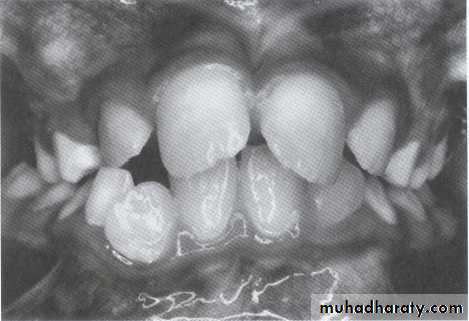

4- One mandibular permanent lateral incisor block out labially and midline discrepancy.5- Bilateral exfoliation of primary mandibular canine.

6- Gingival recession of one or more mandibular incisors.7- Split maxilla.

8- Canine bulging in maxillary and mandibular vestibule.

9- Palisading maxillary molars.UNIVERSITY OF MOSUL